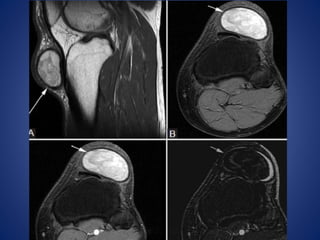

• #10 PTFJ cyst. A 57-year-old man with foot drop. Axial (PD) image (A) shows large cyst (arrows) compressing the common peroneal nerve (arrowhead). There is muscle edema (arrow) in anterior tibialis on the axial STIR image (B)

• #12 Prepatellar bursitis. A 16-year-old female with anterior knee pain. (A) T2W fat-saturated image demonstrates enlarged fluid-filled space in prepatellar region (arrows) with surrounding fat stranding. (B) T1W post-contrast image demonstrates only peripheral enhancement (arrows)

• #13 Infrapatellar bursitis. A 28-year-old male with anterior knee pain. Sagittal fat-saturated T2W image shows triangular pocket of fluid (arrow) between distal patellar tendon and anterior tibia. There is also bone contusion in lateral femoral condyle and fluid in suprapatellar recess (arrowheads), resulting from transient lateral patellar dislocation

• #15 Iliotibial band cyst. A 46-year-old man with palpable abnormality. (A) Coronal T2W fat-saturated image demonstrates well-circumscribed hyperintense cyst (arrows) abutting the iliotibial band, which does not enhance internally following contrast administration on the post-contrast T1W fat-saturated image (B)